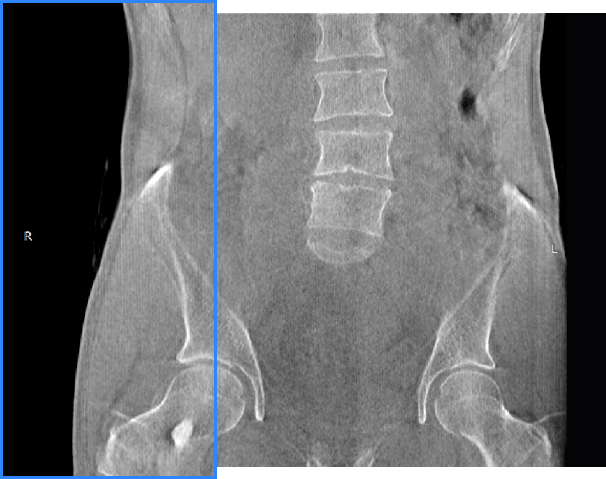

髋关节